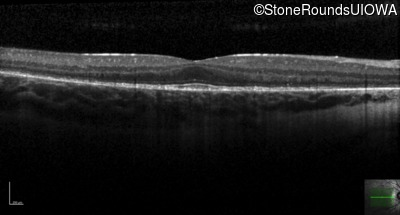

Optical Coherence Tomography - Left - 20/25 -3

Exemplar / OCT Stack